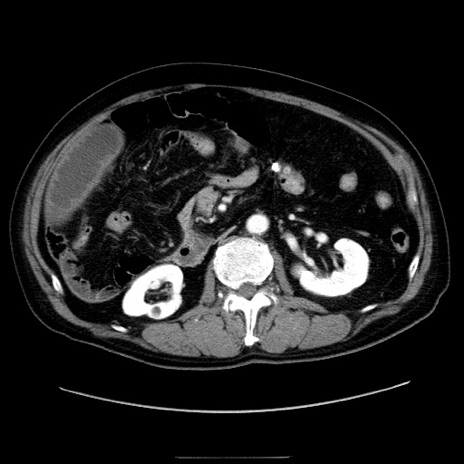

症例30(横断像)

【症例】80歳代男性

【主訴】臍周囲痛

【現病歴】約6時間前から臍下部痛が出現。次第に腹部膨隆・背部痛も生じてきたため来院。背部痛の場所は変化しない。

【身体所見】意識清明、BT 36.3℃、BP  131/87mmHg、P 87bpm、SpO2 100%(RA)、臍周囲自発痛・圧痛あり、反跳痛なし、自発痛部位に一致して板状硬あり、腹部膨隆、腸雑音減弱、CVA tenderness両側陰性。

【データ】WBC 19600、CRP 0.33